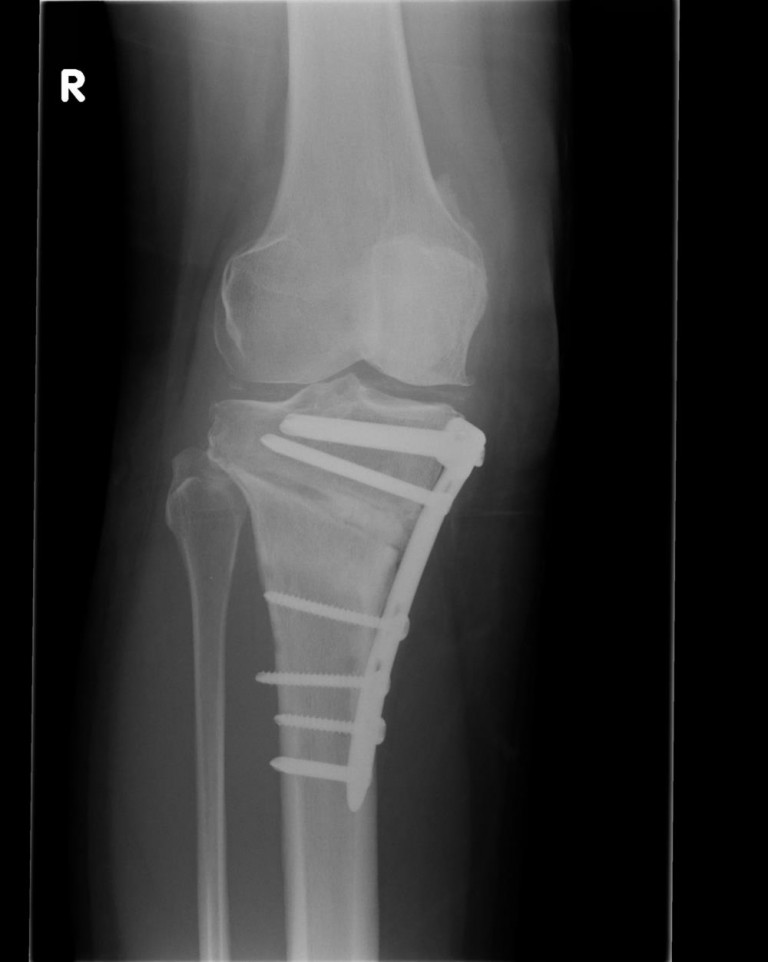

Distal Femoral Osteotomy OrthoFixar 2024 Osteotomy Vs Osteoplasty Osteoplasty is the branch of surgery concerned with bone repair or bone grafting. Periacetabular osteotomy periacetabular osteoplasty is a major surgery that involves repositioning your hip socket. It’s used to correct a congenital hip abnormal formation called hip dysplasia. The name “osseous resective surgery” itself indicates the removal of bone in such a way that a physiological bone contour (explained. Osteotomy Vs Osteoplasty.